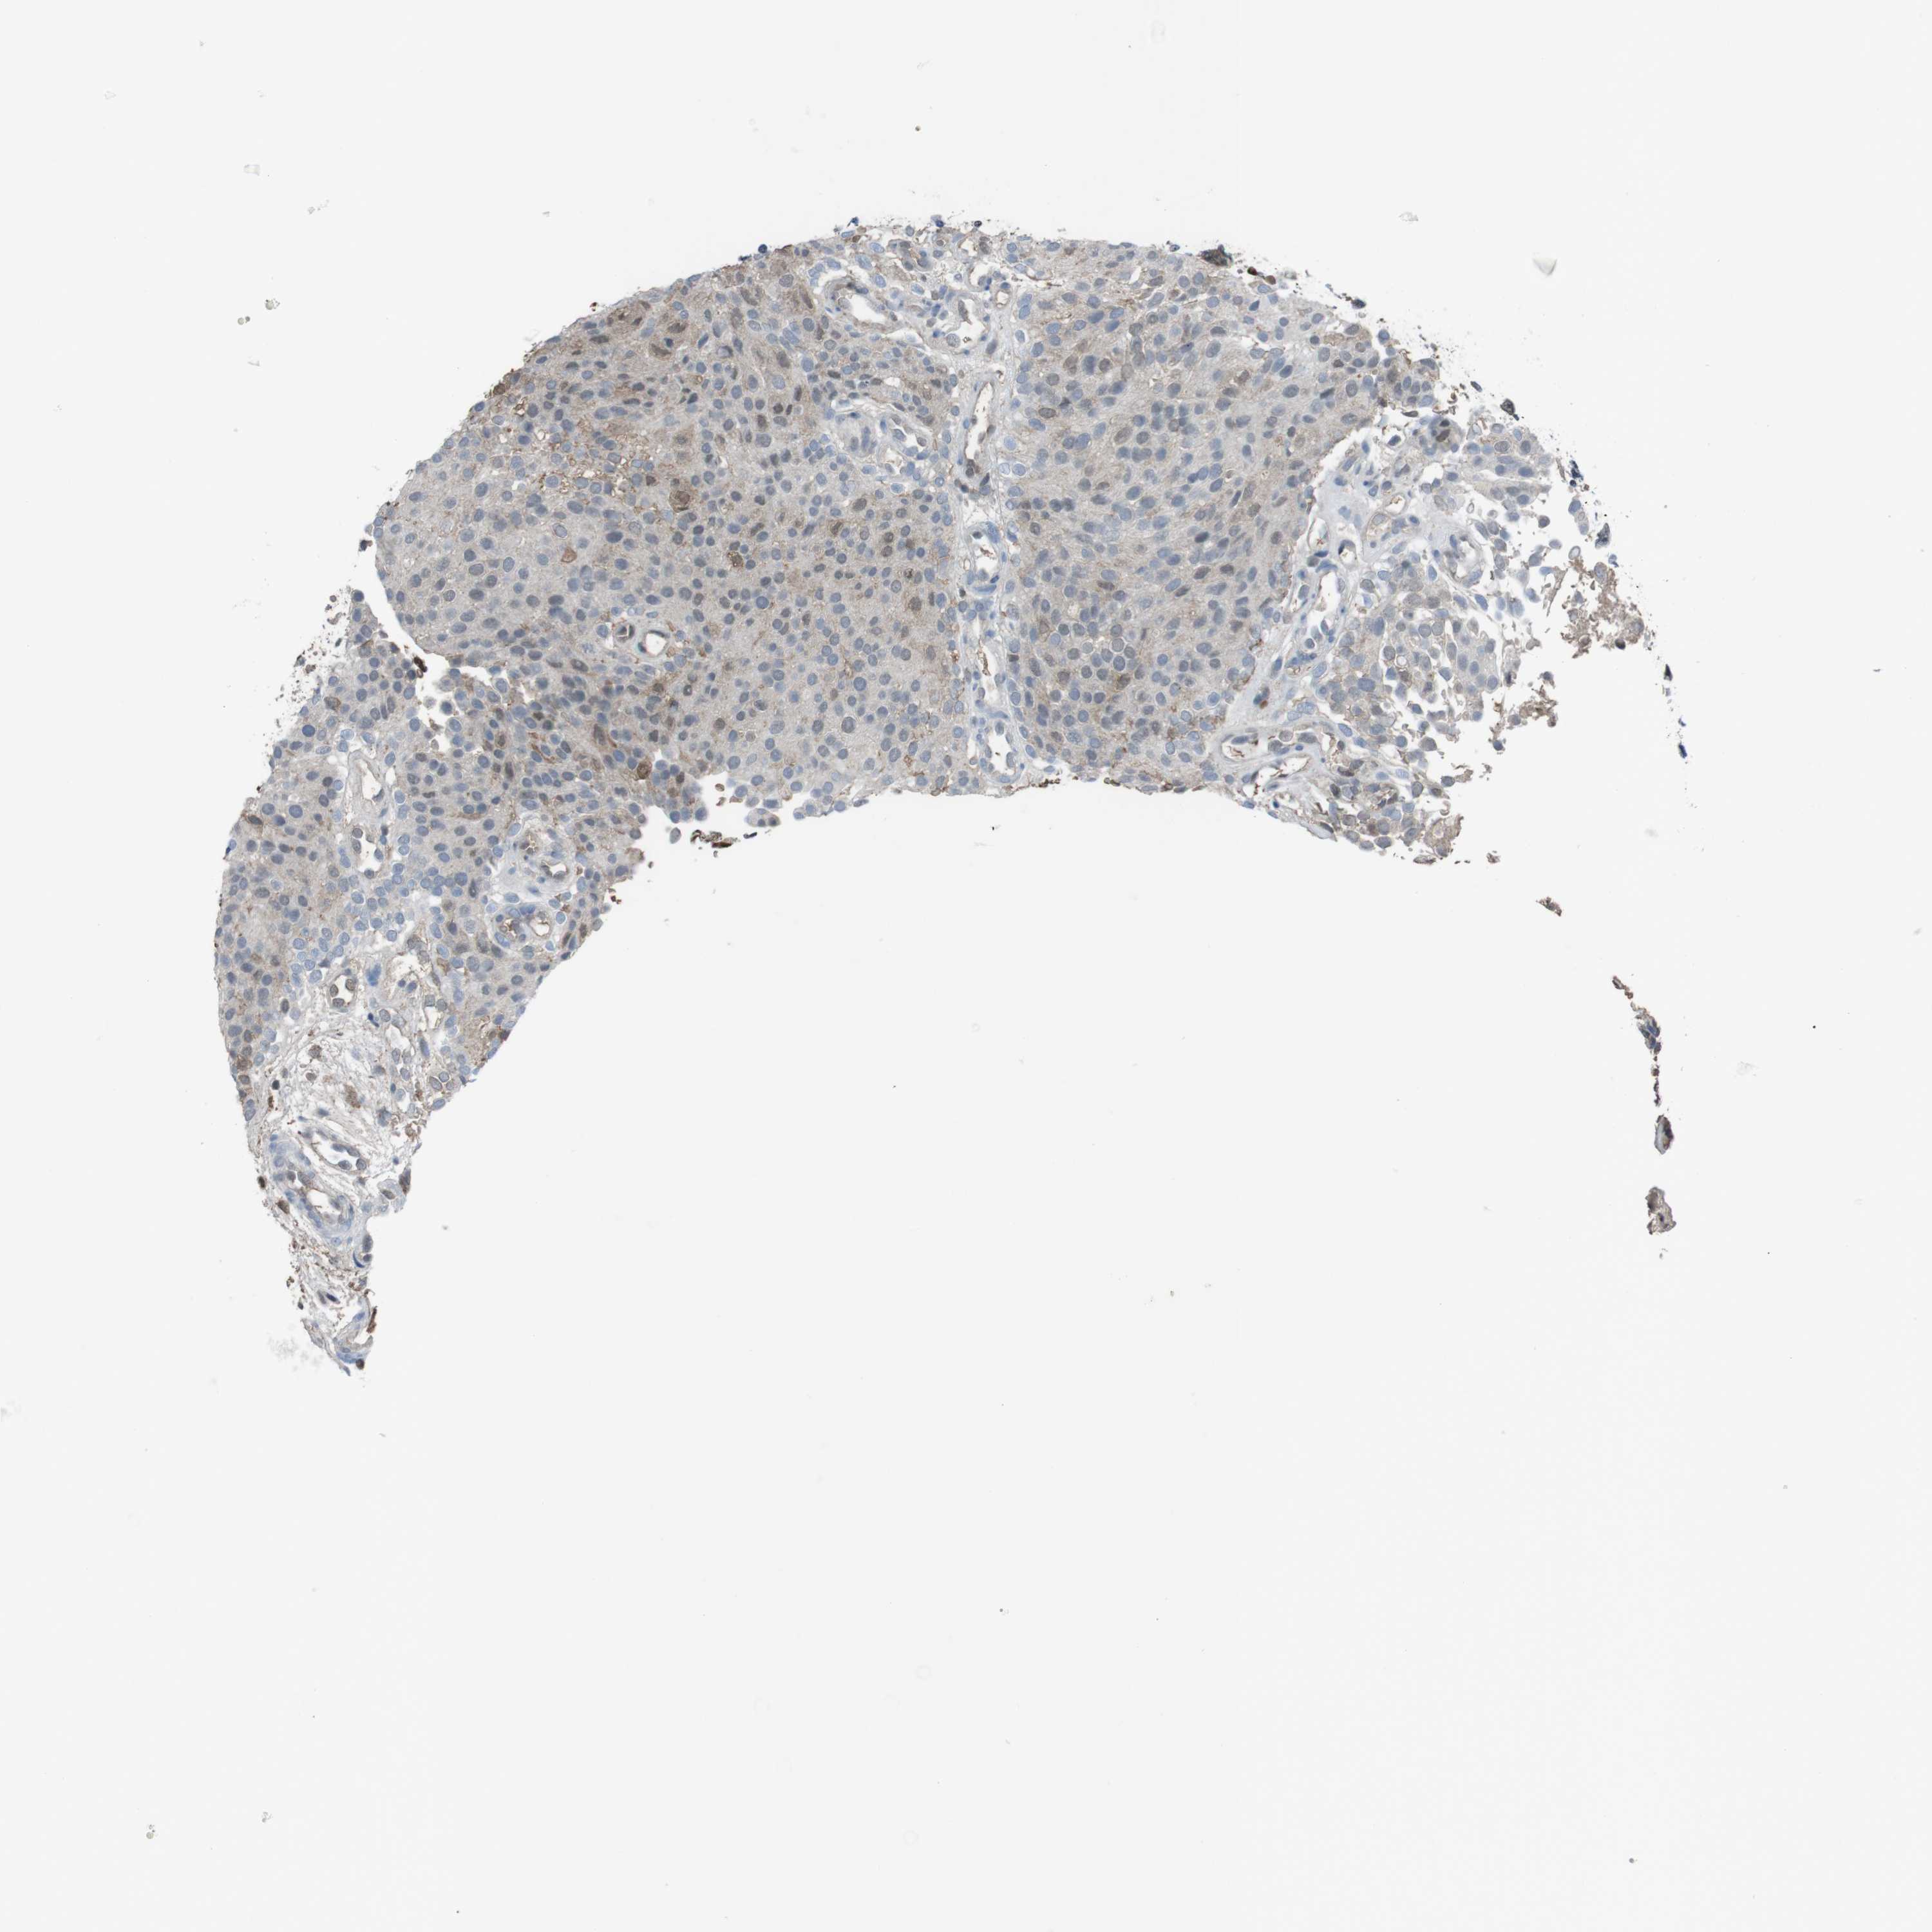

UROTHELIAL CANCER - Protein expressioni

A mouse-over function shows sample information and annotation data. Click on an image to view it in a full screen mode. Samples can be filtered based on level of antibody staining by selecting one or several of the following categories: high, medium, low and not detected. The assay and annotation is described here.

Antibody stainingi

Antibody staining in the annotated cell types in the current human tissue is reported as not detected, low, medium, or high, based on conventional immunohistochemistry profiling in selected tissues. This score is based on the combination of the staining intensity and fraction of stained cells.

Each image is clickable and will lead to virtual microscopy that enables deeper exploration of all samples and also displays staining intensity scores, fraction scores and subcellular localization as well as patient and tissue information for each sample.

Antibody HPA001311

Antibody CAB015351

Staining

High

Medium

Low

Not detected

Intensity

Strong

Moderate

Weak

Negative

Quantity

>75%

75%-25%

<25%

None

Location

Nuclear

Cytoplasmic/membranous

Cytoplasmic/membranous,nuclear

Urothelial carcinoma, High grade

Urothelial carcinoma, Low grade

Adenocarcinoma, NOS